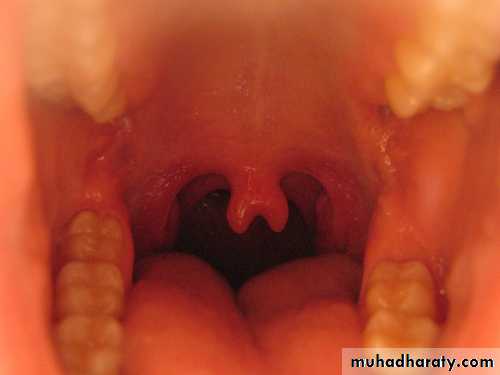

Surface furrowing of tongue (a geographic or scrotal tongue)bifid uvula

Bifid uvula